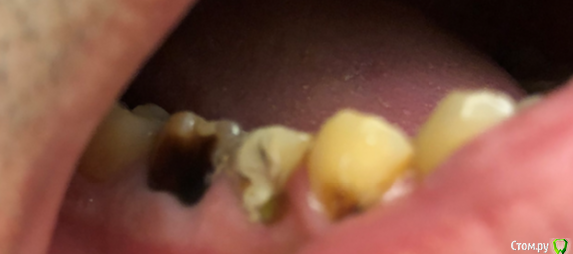

korkor Опубликовано 30 января, 2020 Поделиться Опубликовано 30 января, 2020 (изменено) Недавно заболел зуб. Болел после горячего. Потом просто стал болеть, даже проснулся ночью как-то от боли.Был у стоматолога. Она начала лечить зуб с одним каналом 29 (на фото он правее), так как там кариес был и дырка довольна большая. Рядом с ним 30 (левее) зуб мне лечили лет 10 назад. Сначала стоматолог говорила, что канал до конца недолечили, так как на снимке не видно, плюс инструмент в канале. Но так как у меня одна стенка зуба вся темно-коричневая (давно начал темнеть постепенно, сейчас весь темный), скорее всего там резицин-формалин. Рядом с ним зуб 31 (еще правее), сказала, что якобы может быть трещина в корню посередине зуба (на еще одном снимке там якобы темное уплотнение под корнем). И последний зуб мудрости (32) - там часть зуба откололась.Пролечили мне 29-й зуб с одним каналом. Но боль то есть, то нету. боль в основном ноющая, один день вообще ее нету, на другой опять есть, но слабее, чем была. 1. Помогите разобраться какой зуб может болеть и ответить на вопрос правильно ли мне удалили нерв в 29-м зубе?2. Возможно ли запломбировать 32-й зуб, коренной без удаления нерва? И если нельзя, то что лучше - удалять зуб или прочистить каналы и запломбировать?3. Что посоветуете делать с 30-м зубом (коричневый) и возможна ли боль от трещины (и есть ли трещина) в 31-м зубе? Изменено 30 января, 2020 пользователем korkor Ссылка на комментарий